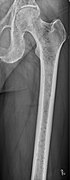

The diagnostic examination of a person with suspected multiple myeloma typically includes a skeletal survey. This is a series of X-rays of the skull, axial skeleton, and proximal long bones. Myeloma activity sometimes appears as "lytic lesions" (with local disappearance of normal bone due to resorption). And on the skull X-ray as "punched-out lesions" (pepper-pot skull). Lesions may also be sclerotic, which is seen as radiodense.[47] Overall, the radiodensity of myeloma is between −30 and 120 Hounsfield units (HU).[48] Magnetic resonance imaging is more sensitive than simple X-rays in the detection of lytic lesions, and may supersede a skeletal survey, especially when vertebral disease is suspected. Occasionally, a CT scan is performed to measure the size of soft-tissue plasmacytomas. Bone scans are typically not of any additional value in the workup of people with myeloma (no new bone formation; lytic lesions not well visualized on bone scan).

Femur with multiple myeloma lesions

Same femur before myeloma lesions for comparison